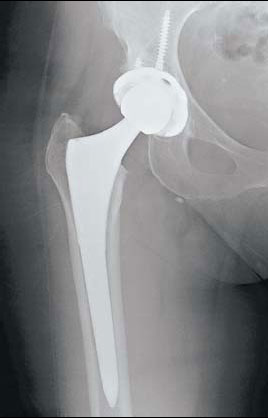

Patients told of better love lives after joint replacement. Derek Berwin / Getty Images |

Hip replacement surgery has risen 85 percent in the past decade, with doctors in the United States performing more than 300,000 procedures in 2010, the latest year for which statistics are available. But these are not your grandmother's hips. Much of the increase in hip surgery has been fueled by active middle-age adults, 45 to 65. In that age group, hip replacements have nearly tripled to 128,000 during the same period.